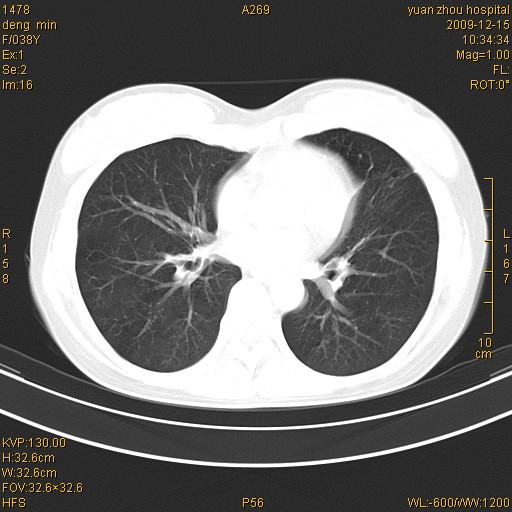

标题: CT23919:F38Y 咳嗽月余 [打印本页]

标题: CT23919:F38Y 咳嗽月余

右肺中下叶、左肺上叶舌段及左肺下叶支气管扩张合并感染。